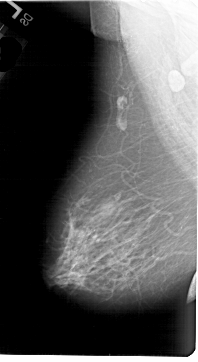

A_1646_1.RIGHT_CC

RIGHT_MLO LINES 6331 PIXELS_PER_LINE 3736 BITS_PER_PIXEL 12 RESOLUTION 43.5 OVERLAY